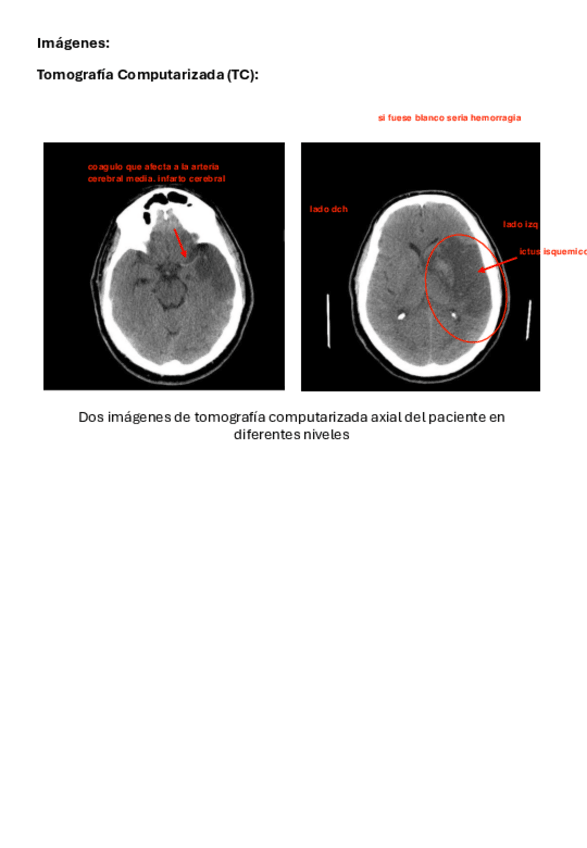

He publicado nuevos examenes de 3º Imágenes Biomedicas: PREGUNTAS-1ER-PARCIAL.pdf